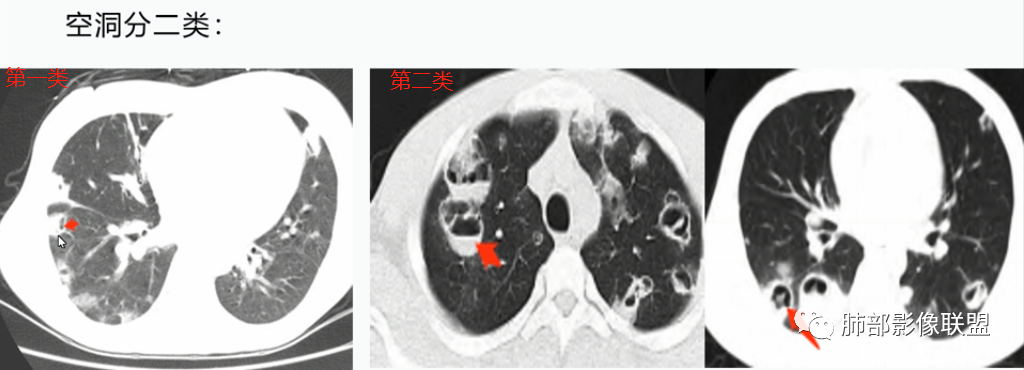

3.空洞:分为两类。

第一类,偏心空洞,一侧壁厚,周围实变明显。

第二类,薄壁空洞(偏中后期):壁薄且均匀,内外壁光滑,张力高,内有气液平面、间隔影,各空洞相对独立互不相通

4.囊:张力高,壁薄,内外壁光滑,可有间隔